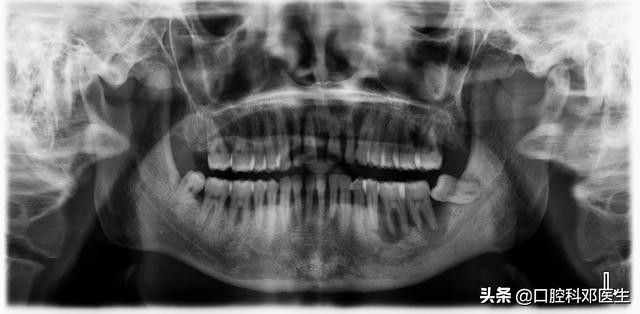

5.X片显示:牙床骨头有不同程度的吸收,尤其是左侧下颌磨牙,阴影较大。